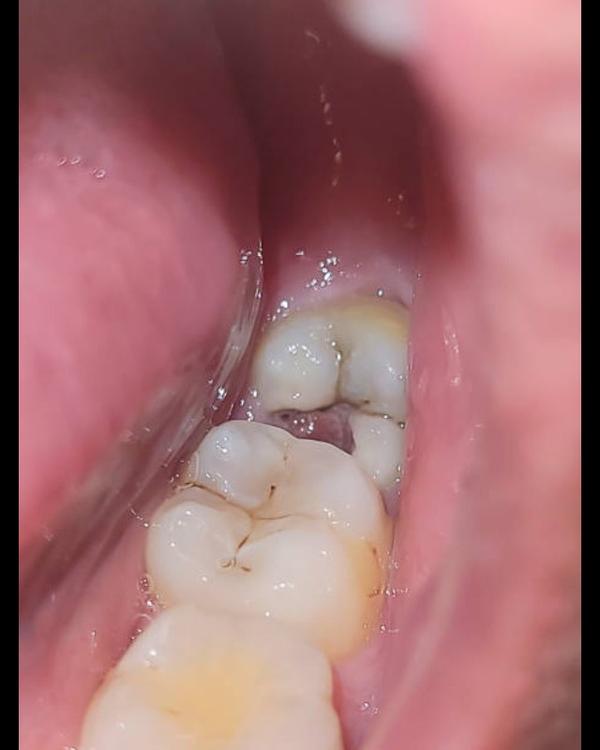

Whats wrong with your teeth ? wisdom tooth pain